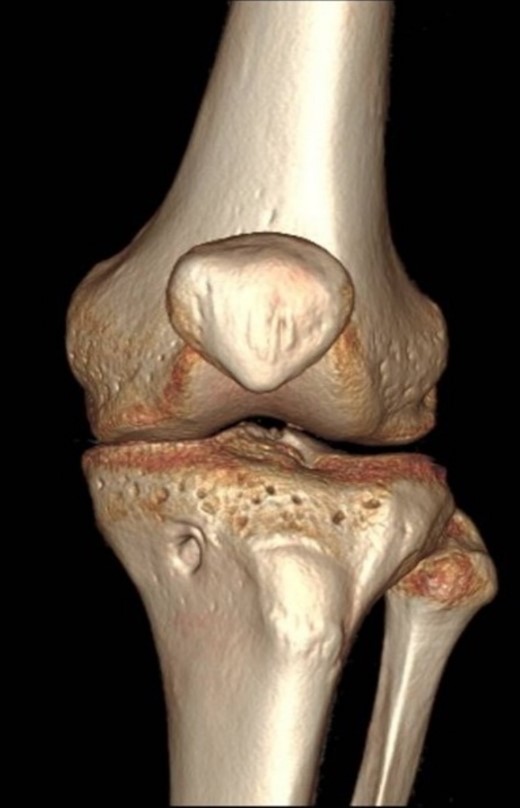

A 23-year-old male veterinarian presented to our out-patient department postright ACL reconstruction with hamstring autograft, PHMM tear by all-inside repair via sMCL pie-crusting technique, and lateral extra-articular tenodesis (modified Lemaire) in June 2023. A preoperative plain radiograph of the right knee revealed no evidence of HO (Fig. 1). No evidence of heterotopic ossification was detected in the right knee on plain radiographs taken 2 weeks postsurgery. (Fig. 2). Five months postsurgery, plain radiographs revealed new bone formation at the medial femoral condyle, precisely where the sMCL femoral origin was located (Fig. 3). The patient was asymptomatic and continued with rehabilitation. Seven months after the surgery, the patient started to complain of pain and clicking sensations when the right knee was flexed beyond an angle of 130°. Magnetic resonance imaging revealed consolidation of the newly formed bone, leading to a diagnosis of HO post-sMCL pie-crusting (Fig. 4). Nine months following surgery, the patient began to feel a bony mass on the medial side of the right knee. A plain radiograph and computed tomography (CT) scan revealed the complete formation of a bone island (Fig. 5). The past surgical history of this patient revealed that he had undergone left knee ACL reconstruction with hamstring autograft in December 2021, which failed and was complicated by a PHMM tear. The patient had presented to our facility for a revision. A revision ACL reconstruction was done using a bone-tendon-bone (BTB) autograft and PHMM tear all-inside repair via the sMCL pie-crusting technique in February 2022. A 2-year follow-up of the left knee, including physical examination and 3D-CT scans (Fig. 6), revealed no symptoms or signs of HO, although the same technique of sMCL pie-crusting was employed. Our patient suffered no head trauma during treatment. Past medical, drug, allergy, family, social histories, and reviews of systems were irrelevant to our case.

Plain radiograph of right knee AP (A), internal rotation AP (B), CT scan coronal view (C), and axial view (D) 9 months postoperative showing fully mature HO.